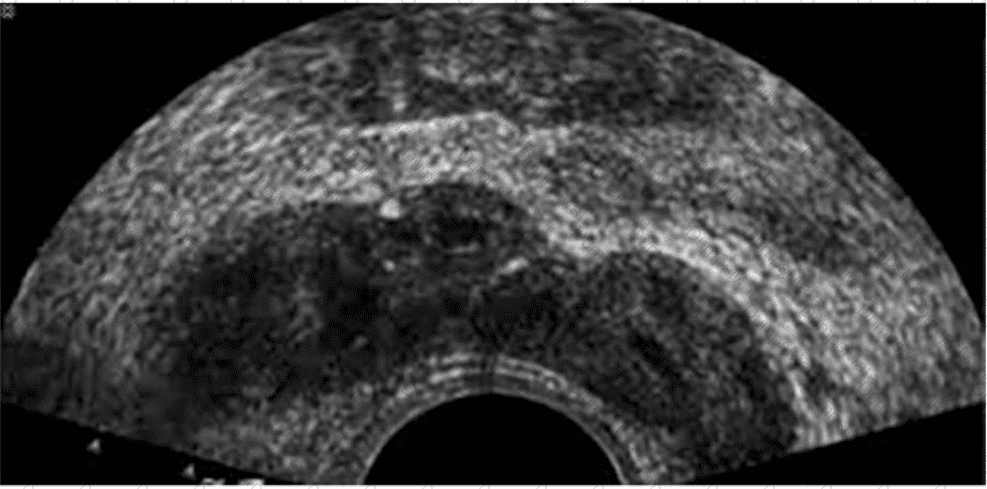

Which condition is most consistent with the findings in this image?

AB-Abdomen Question 28

Options:

A.

Fungal balls

B.

Renal cell carcinoma

C.

Acute pyelonephritis

D.

Medullary sponge kidney